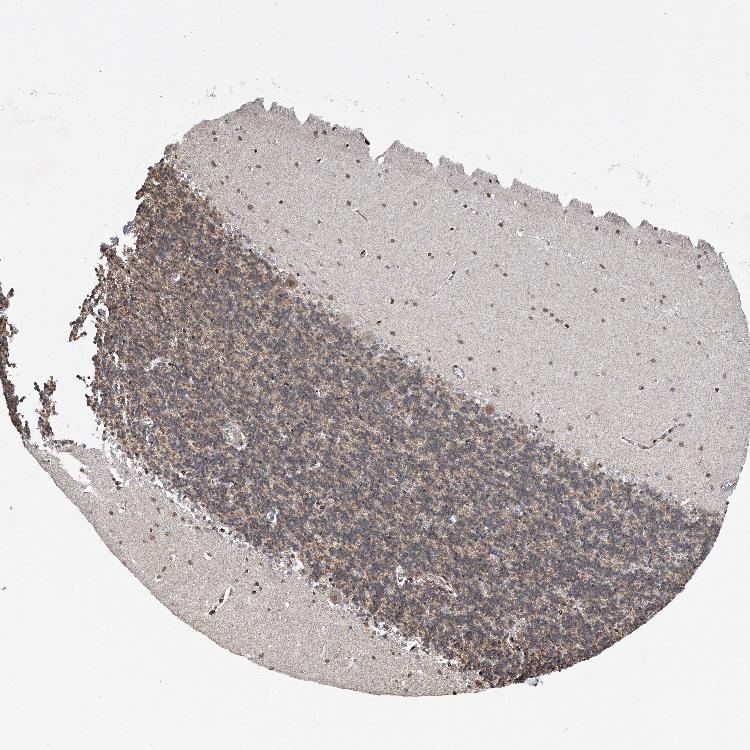

BRAIN CEREBELLUM Show tissue menu

CEREBELLUM - Expression summary

CEREBELLUM - Antibody stainingi

Antibody staining in the annotated cell types in the current human tissue is reported as not detected, low, medium, or high, based on conventional immunohistochemistry profiling in selected tissues. This score is based on the combination of the staining intensity and fraction of stained cells.

Each image is clickable and will lead to virtual microscopy that enables deeper exploration of all samples and also displays staining intensity scores, fraction scores and subcellular localization as well as patient and tissue information for each sample.

Antibody HPA029619Antibody HPA029621

Purkinje cells Not detectedMedium

Cells in granular layer Not detectedMedium

Cells in molecular layer Not detectedHigh